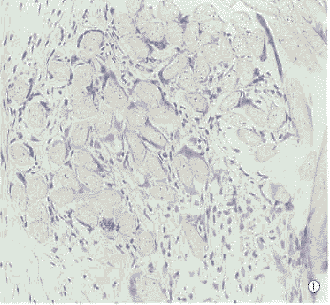

第2组第10天即可见到植入物纤维之间新生血管、纤维细胞分隔深入,炎性细胞少,可见异物巨细胞。随着时间延长,成纤维细胞及结缔组织伸入到植入片各纤维之间,第90天全部形成了植入片纤维与自身结缔组织互相交织的形态结构(图1)。

第3组植入片与巩膜之间以及植片结构间隙有较多的炎性细胞,随着时间延长,炎性细胞成分减少,植入片与巩膜之间可见潜在腔隙。植入物结构与巩膜的区别明显(图2)。

图1 术后第90天,植入的心包补片纤维与结缔组织相互交织(HE×20) 图2 术后第90天,血管补片与宿主巩膜仍不粘连,二者之间存在腔隙(HE×20) Fig.1 On d 90 after implanted surgically,the fibers of artificial pericardium are interwoven with connective tissue(HE×20) Fig.2 On d 90 after implanted sturgically,there was a gap between artificial vessel band and host scleral(HE×20)